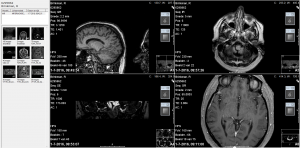

Ruim 12 uur onderweg geweest en 578 kilometers gereden (Leeuwarden-Antwerpen vv) zijn wij (mijn vrouw en ik) blij maar wel moe dat we dit bezoek aan professor dr. Floris Wuyts werkzaam aan het UZA te Antwerpen hebben volbracht. Het heeft mij in ieder geval een nieuwe diagnose opgeleverd nl. Vestibulaire Paroxysmien (VP).Na een intake gesprek met NKO arts Van Haesendonck-Gilles en professor Wuyts, heb ik mijn verzamelde medische gegevens, een gedetailleerde overzicht van de evenwichtsstoornissen vanaf 2012 tot heden en een ingevulde SO STONED formulier ter beschikking gesteld, zodat er een grote hoeveelheid gegevens aanwezig was omtrent mijn ziekteverloop. Vervolgens heb ik nog een uitgebreide gehoortest gedaan en tenslotte kreeg ik een bril op waardoor Floris mijn oog bewegingen kon zien door mij in een verschillende houdingen te plaatsen. Als er een vorm van duizeligheid of misselijk gevoel optreedt is het zichtbaar op het scherm (zie foto’s).

Bij de foto’s: Professor dr. Floris Wuyts onderzoekt mij en kijkt naar de oogbewegingen op het scherm.